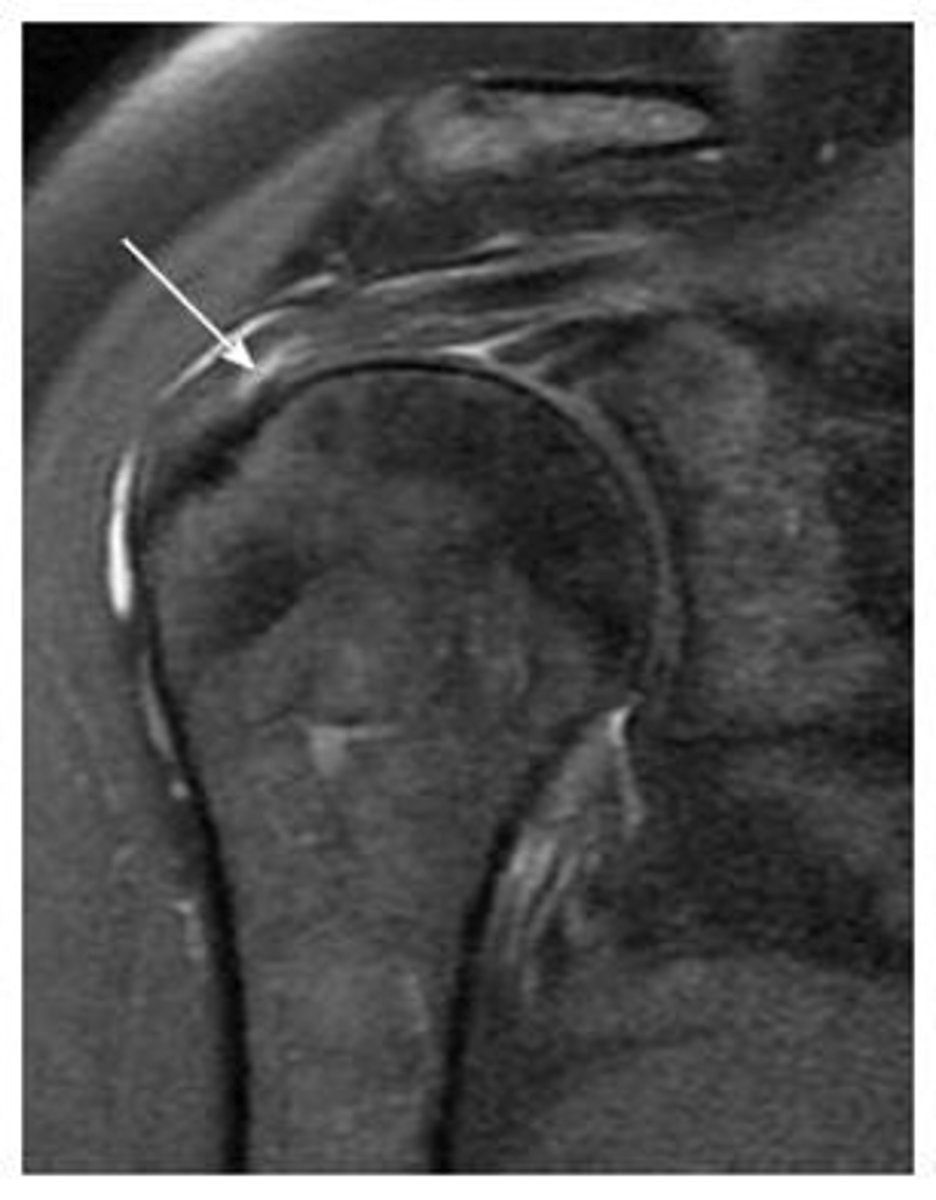

Rotator cuff tendinopathy -- image involves signal changes but the tendon is NOT yet torn

What is this image depicting w/ the rotator cuff? How do you know?

Partial tear of the rotator cuff -- focal area of disruption